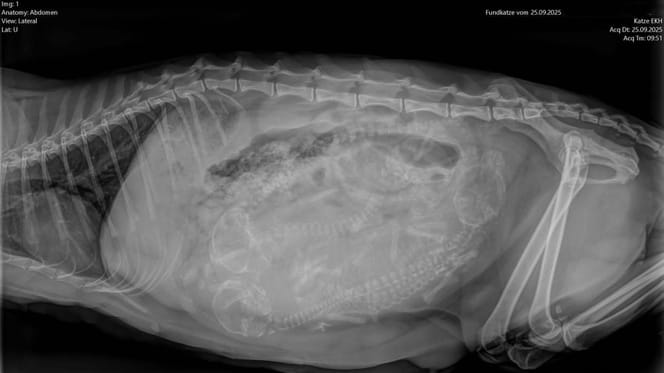

© Tierheim Bochum / Facebook

Zoals bij alle nieuw opgenomen dieren, voeren de dierenverzorgers een grondig onderzoek uit. Daarbij valt iets op: de kat bewoog zich stijf, alsof ze pijn had. Om zeker te zijn, wordt er een röntgenfoto gemaakt en het resultaat is vernietigend.

De botten van de kat vertonen duidelijke vervormingen – een typisch teken van het fokken van kwalen-ras Scottish Fold. De schattige, naar voren gevouwen oren, die veel mensen zo charmant vinden, zijn het resultaat van een genetische mutatie. Het veroorzaakt chronische bot- en gewrichtsschade, een leven lang.